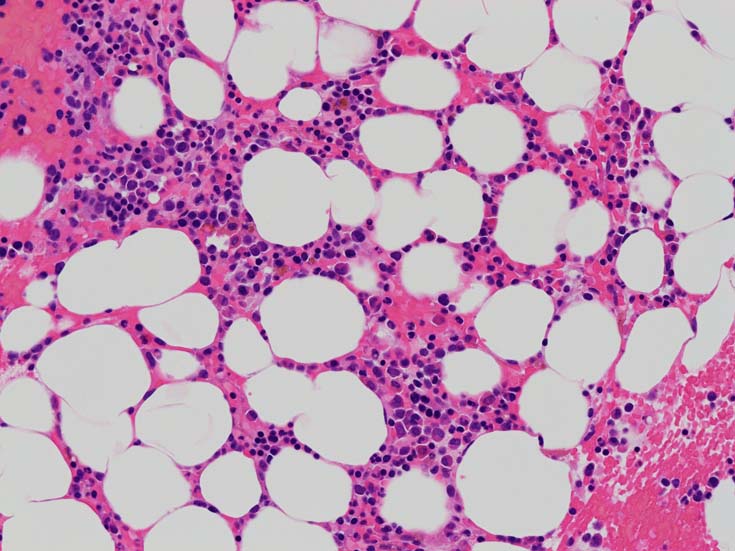

骨髄赤芽球のHbF発現

MDS症例のHbF発現.

サムネイル画像をクリックすると大きな画像が見られます.

MDSでの赤芽球HbF発現は, 陽性細胞はそれほど多くない印象ですが, この低形成性MDS症例では, 多くの陽性細胞がaggregatesを形成していました.